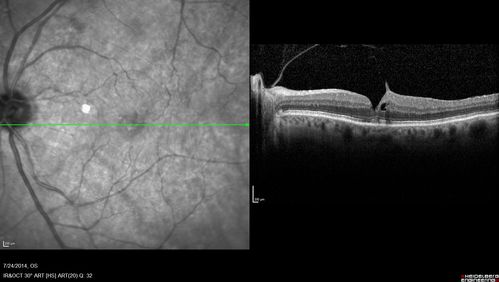

Macular Hole Left Eye - progression from VMT - Stage II macular hole - Spontaneously Closed Macular Hole

Vision has improved to 20/40 and the hole is closed